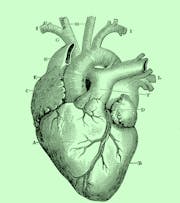

Hjertets anatomi

Er hjertet kroppens vigtigste organ eller en simpel, blodpumpende muskel? Tre forskere dissekerer, hvordan vores kulturelle, medicinhistoriske og videnskabelige blik på hjertet har udviklet sig gennem tiden.

På Bloom dykker videnskabshistoriker Karin Tybjerg og kardiologerne Emil Loldrup Fosbøl og Peter Karl Jacobsen ned i hjertets anatomi. For måske hjertet og de mange kilometer af arterier og vener, som udgør hjerte-karsystemet, alligevel fortjener sin ophøjede position? Og kan den nyeste forskning være med til at sikre, at færre hjerter vil stoppe med at slå i fremtiden?